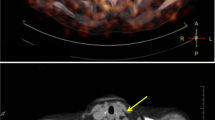

In vivo PET/CT scans of ApoE KO-cuff mice were acquired 9, 12, and 15 weeks after surgery. The time points for imaging were chosen based on the time course of plaque development and the time needed to reduce post-surgical inflammation in this mouse model as assessed by [18F]FDG (data not shown). ApoE KO-cuff HFD mice were injected with either [11C]AM7 or [18F]AC74 (Fig. 1b), a fluorine-18 labeled analog of [11C]AM7 with 10-fold lower binding affinity to hCD80 (A. Chiotellis et al., manuscript in prep.), or [18F]FDM, and every mouse was additionally scanned with [18F]FDG. This resulted in a higher number of animals scanned with [18F]FDG than with the other tracers. For the CD80-specific tracer [11C]AM7, a higher standardized uptake value (SUV) in both US and DS plaques of the cuff than the background (neck) region was observed at all three time points, indicating an accumulation in atherosclerotic plaques (Figs. 6 and 7). Differences were significant at 9 weeks after surgery. The uptake of the CD80 radiotracer candidate [18F]AC74 was similar in plaque and background regions and was independent of the time point. Even at later time points (19 weeks after surgery), when plaque size increased more, [18F]AC74 did not significantly accumulate in plaques (data now shown). [18F]FDG and [18F]FDM displayed significantly higher SUV values in the cuff US and DS segments than the background. A significant difference in SUV values between the US and DS segments was only determined for [18F]FDG 12 weeks after surgery, with higher uptake in the US segment. The quantification of tracer accumulation in the aortic arch was hampered by the radioactivity spill over from the high liver uptake of [11C]AM7 and [18F]AC74 and high myocardial uptake of [18F]FDG and [18F]FDM, respectively.

In vivo CT (gray scale) and PET/CT slices of the neck region of ApoE KO mice (15 weeks post surgery) after injection of either a [11C]AM7, b [18F]AC74, c [18F]FDG, or d [18F]FDM. Crosshair indicates cuff and control as clearly visible in CT images. The maximal standardized uptake value (SUV) is 0.3 for [11C]AM7 and [18F]AC74 and 0.5 for [18F]FDG and [18F]FDM. Images were averaged from 1 to 61 min post injection of [11C]AM7 and [18F]AC74 and from 30 to 60 min post injection of [18F]FDG and [18F]FDM.